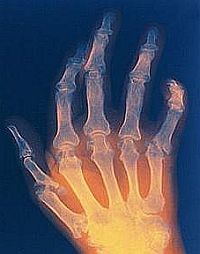

Az artritisz az ízületeket érintő gyulladásos megbetegedés.

Általános tünete az ízületekben jelentkező fájdalom és merevség, valamint duzzanat, bőrpír és melegség is felléphet. Akadályozottá válik az ízületek mozgása. Az atrtitisz igen sok, 65 év feletti idős embernél előfordul, de bármely életkorban kialakulhat.

A kopásos artritisz esetén az ízületi porc fokozatos elvékonyodása miatt az ízületi felszínek egyre kevésbé csúsznak el egymáson, ami fájdalmat, merevséget és mozgásbeszűkülést okoz. Ez a forma leggyakrabban a térdet, a csípőt, a kéz kisízületeit és a gerincet érinti. A fájdalom jellemzően terhelésre fokozódik, pihenésre enyhül, és reggelente inkább csak rövid ideig tartó merevség jelentkezik.

A reumatoid artritisz ezzel szemben az immunrendszer zavarán alapul: a szervezet saját ízületi szövetei ellen fordul, tartós gyulladást okozva. Ilyenkor a reggeli merevség gyakran egy óránál is tovább tart, a fájdalom nyugalomban sem szűnik meg teljesen, és a gyulladás nemcsak az ízületeket, hanem más szerveket – például a szívet, a tüdőt vagy a szemet – is érintheti. A betegség lefolyása hullámzó, fellángolásokkal és nyugalmi időszakokkal.

Az artritisz járhat együtt duzzanattal?